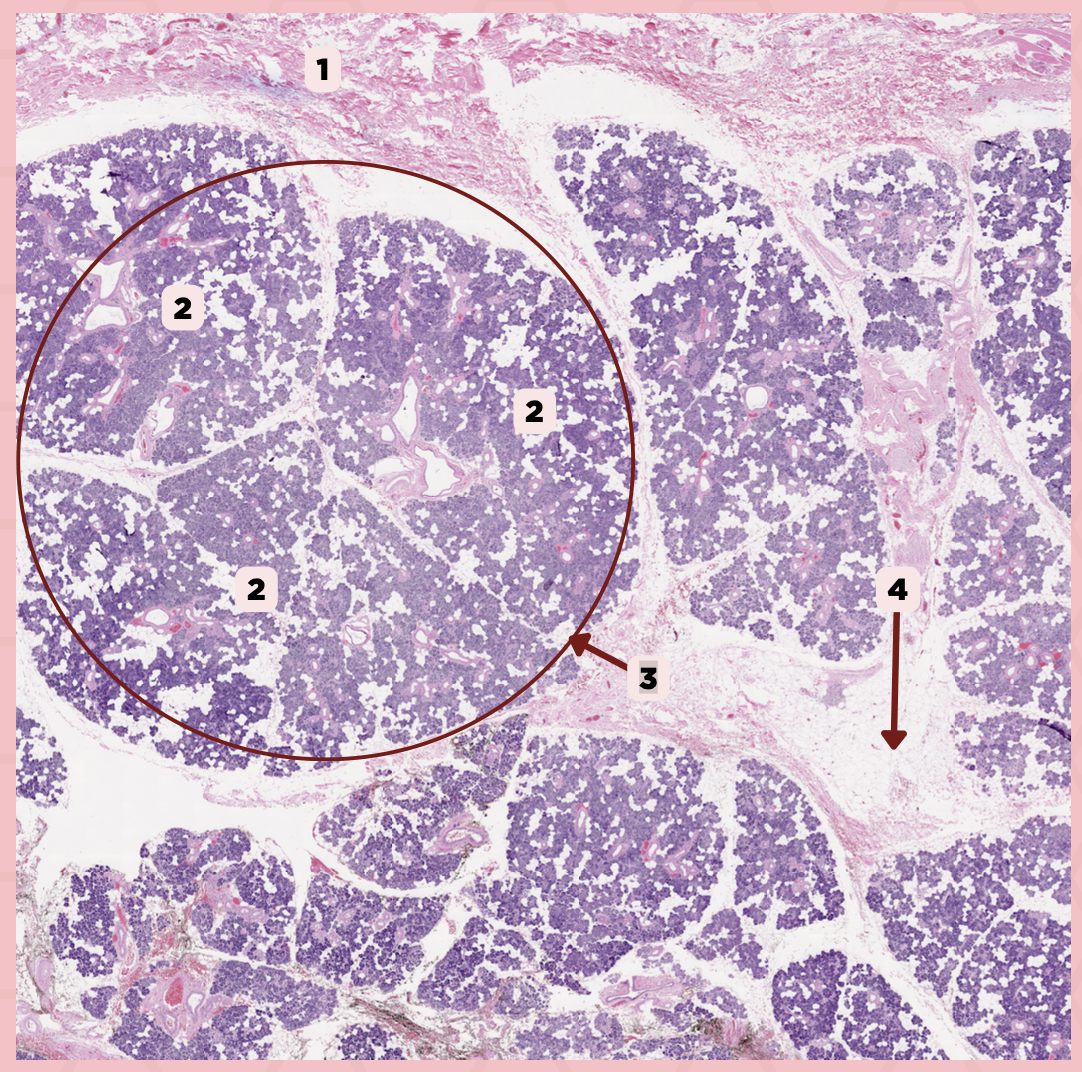

Parotid

Identify the specimen.

Capsule

Identify the structure labeled as 1.

Septa

Identify the structure labeled as 2.

Lobule

Identify the structure labeled as 3.

Lymph Node

Identify the structure labeled as 4.